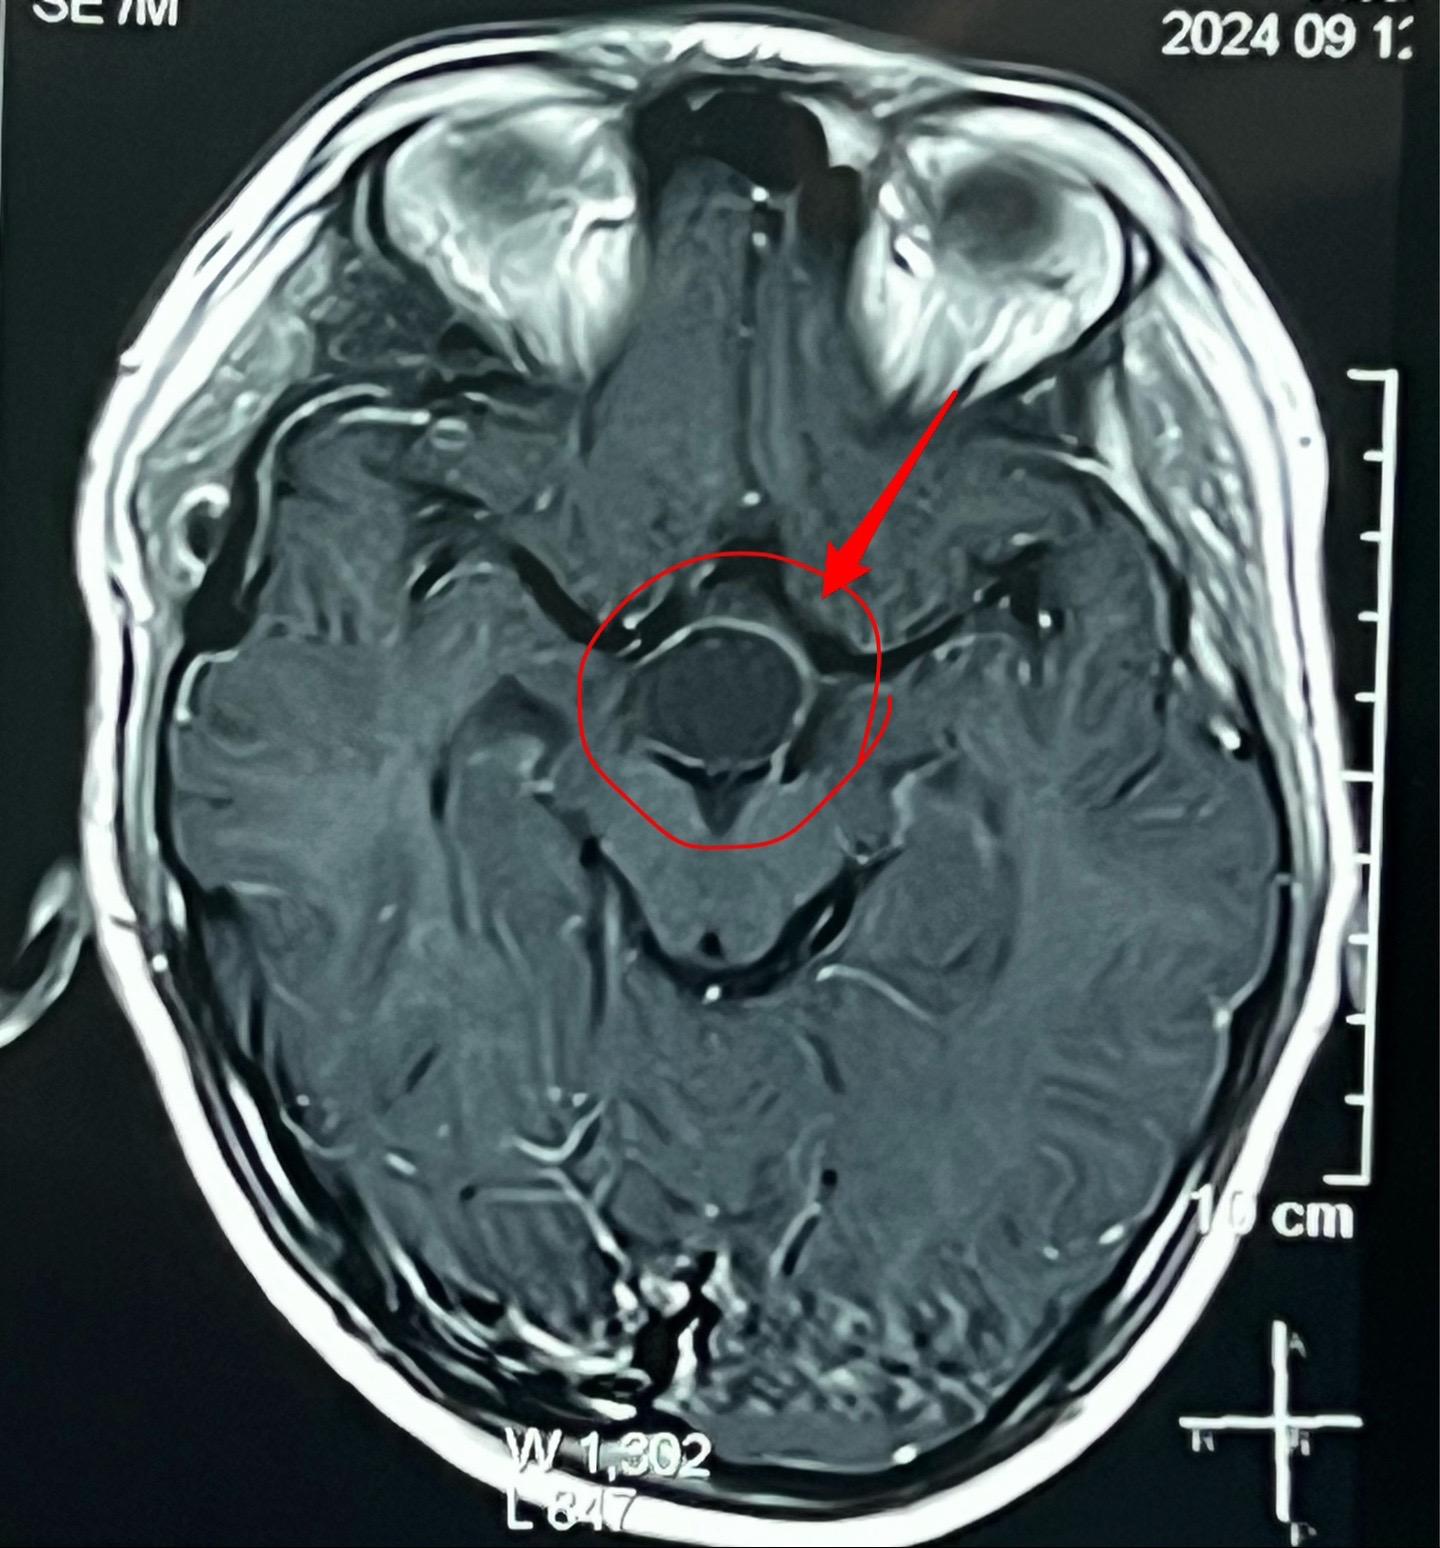

国庆节长假后第一天完成两个手术。一个手是33岁女性,来自云南省香格里拉。因左眼视力下降,到医院检查发现鞍区肿瘤,怀疑是颅咽管瘤。病人没有内分泌功能障碍。影像学上肿瘤是实性的,没有钙化,而且可以看见垂体信号。到底是什么肿瘤呢?今天手术中取肿瘤标本作快速冰冻病理检查,报告是垂体瘤。肿瘤得到完全切除,手术后病人视力好转了。 另一个手术是11岁男孩子,颅咽管瘤复发。经原切口翼点入路将肿瘤完全切除。术前磁共振只看见一个圆形肿瘤,术中发现除了这个肿瘤外还有5个散在的钙化斑,均得到完全切除。这样的散在钙化斑是潜在的危险因